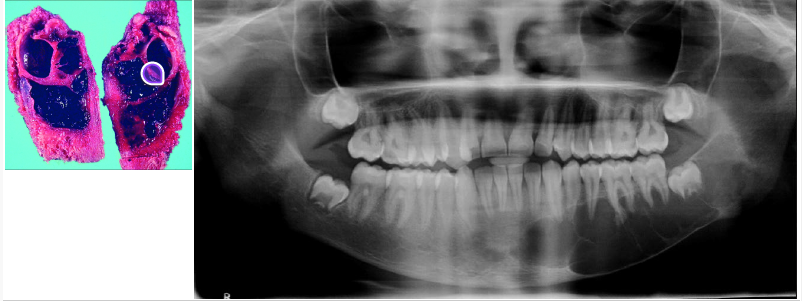

cemento-osseous dysplasia

a benign fibro-osseous lesion of the jaw

a common fibro-osseous lesion that occurs in the tooth-bearing areas of the jaws

in this setting “dysplasia” does not imply that the lesion if precancerous

periapical

focal

florid

periapical cemento-osseous dysplasia

not a neoplasm

adult females

black population (70% of cases)

periapical region of anterior mandible

asymptomatic

early lesions mimic periapical inflammatory pathology (early is radiolucent)

involved teeth are vital

focal cemento-osseous dysplasia

asymptomatic, found incidentally on radiographs

female predilection (30-50 years of age)

more common in white population

posterior mandible, most common location

florid cemento-osseous dysplasia

involvement of multiple quadrants in the maxilla and mandible

most often seen in black women

treatment is often unnecessary

osteomyelitis as one complication in edentulous patients